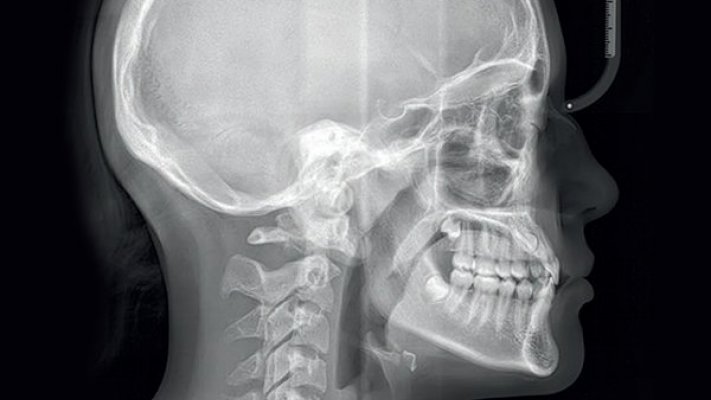

Cientistas russos da Universidade Estatal de Novosibirsk (NGU) encontraram evidências, através de uma tomografia computorizada (TAC), de uma complexa cirurgia maxilofacial realizada há aproximadamente 2500 anos numa mulher da cultura Pazyryk.

"Cientistas da NGU encontraram vestígios de uma operação cirúrgica durante uma tomografia computorizada do crânio de uma mulher da cultura Pazyryk", sublinhou a universidade em comunicado.

"A tomografia computorizada foi uma ferramenta fundamental para o estudo do crânio da mulher. Graças a esta tecnologia, conseguimos ultrapassar o principal obstáculo: os tecidos moles mumificados que obscureciam a estrutura óssea", realçou Vladimir Kanigin, chefe do laboratório de medicina física da NGU.

Segundo o cientista, "a tomografia computorizada permitiu 'remover' virtualmente um modelo digital e, de seguida, um modelo físico 3D do crânio, possibilitando o seu estudo antropológico detalhado".

O estudo não só revelou as consequências da lesão grave, que incluiu uma deformação de 6 a 8 milímetros do osso parietal direito, "mas também detalhes minuciosos, invisíveis num exame padrão".